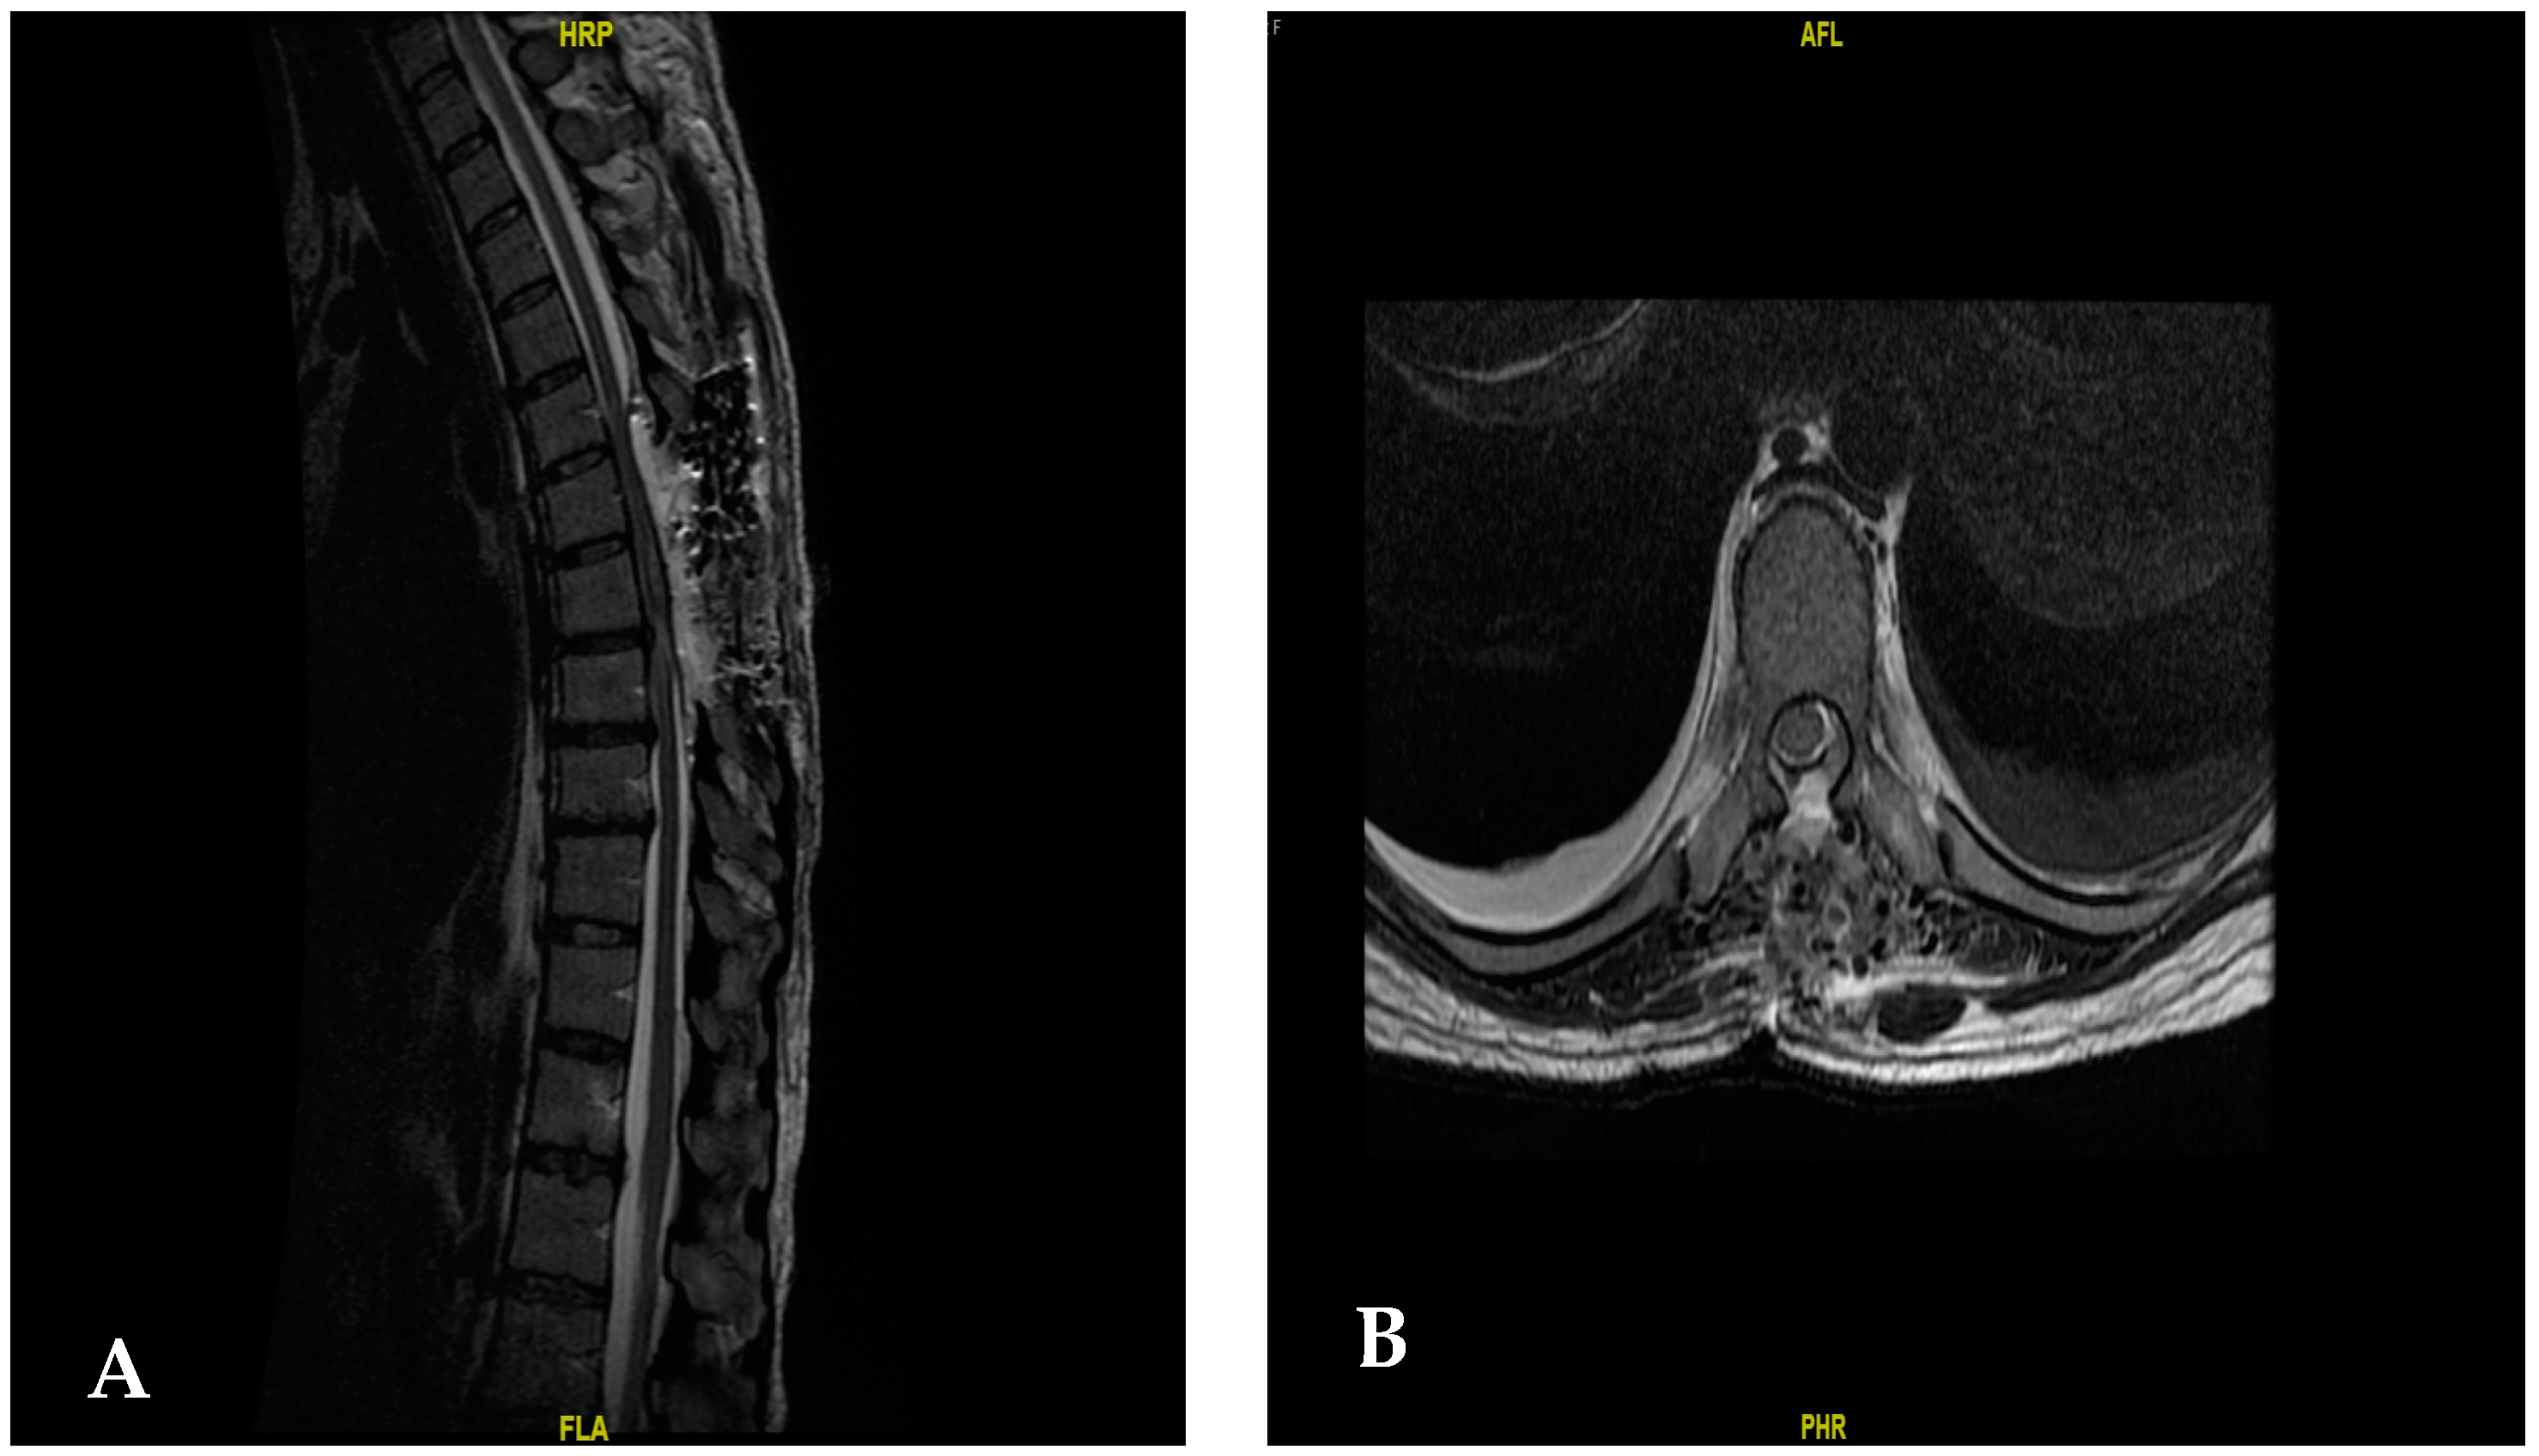

2. Case Presentation